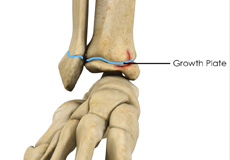

Growth Plate Fracture

Growth plates are areas of soft, cartilaginous tissues present at the end of long bones in growing children. These cartilage tissues or soft bones later harden to become solid bones in adulthood once growing has completed.